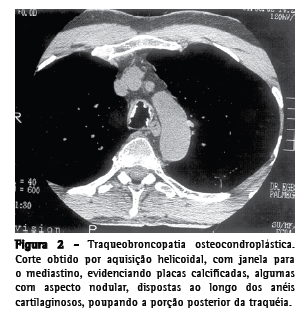

Traqueobroncopatia osteocondroplástica

A traqueobroncopatia osteocondroplástica é uma doença benigna da árvore traqueobrônquica, de etiologia desconhecida, caracterizada pela presença de múltiplos nódulos osteocartilaginosos submucosos, localizados principalmente nas paredes anterior e lateral da traquéia e nos brônquios principais. A parede traqueal posterior geralmente não é acometida.(1,8-12) Muitos pacientes são assintomáticos, sendo a doença, nestes casos, diagnosticada em exames de rotina.(3) Os sintomas mais comuns são tosse, dispnéia, sibilos e, ocasionalmente, hemoptise, causada pelo atrito entre os nódulos.(9) Freqüentemente os pacientes apresentam infecções respiratórias de repetição.(8,9) Embora a traqueobroncopatia osteocondroplástica seja uma doença benigna, algumas vezes ela pode evoluir para estenose traqueal grave.(1,9) A TC é muito sensível na identificação da calcificação dos nódulos, na definição da extensão e distribuição das estenoses traqueobrônquicas, assim como na caracterização das complicações, como atelectasias, bronquiectasias e pneumonias pós-obstrutivas.(10) O achado tomográfico mais comum é a presença de múltiplos nódulos submucosos, calcificados ou não, localizados nas paredes anterior e lateral da traquéia(1,3,9-12) (Figura 2).